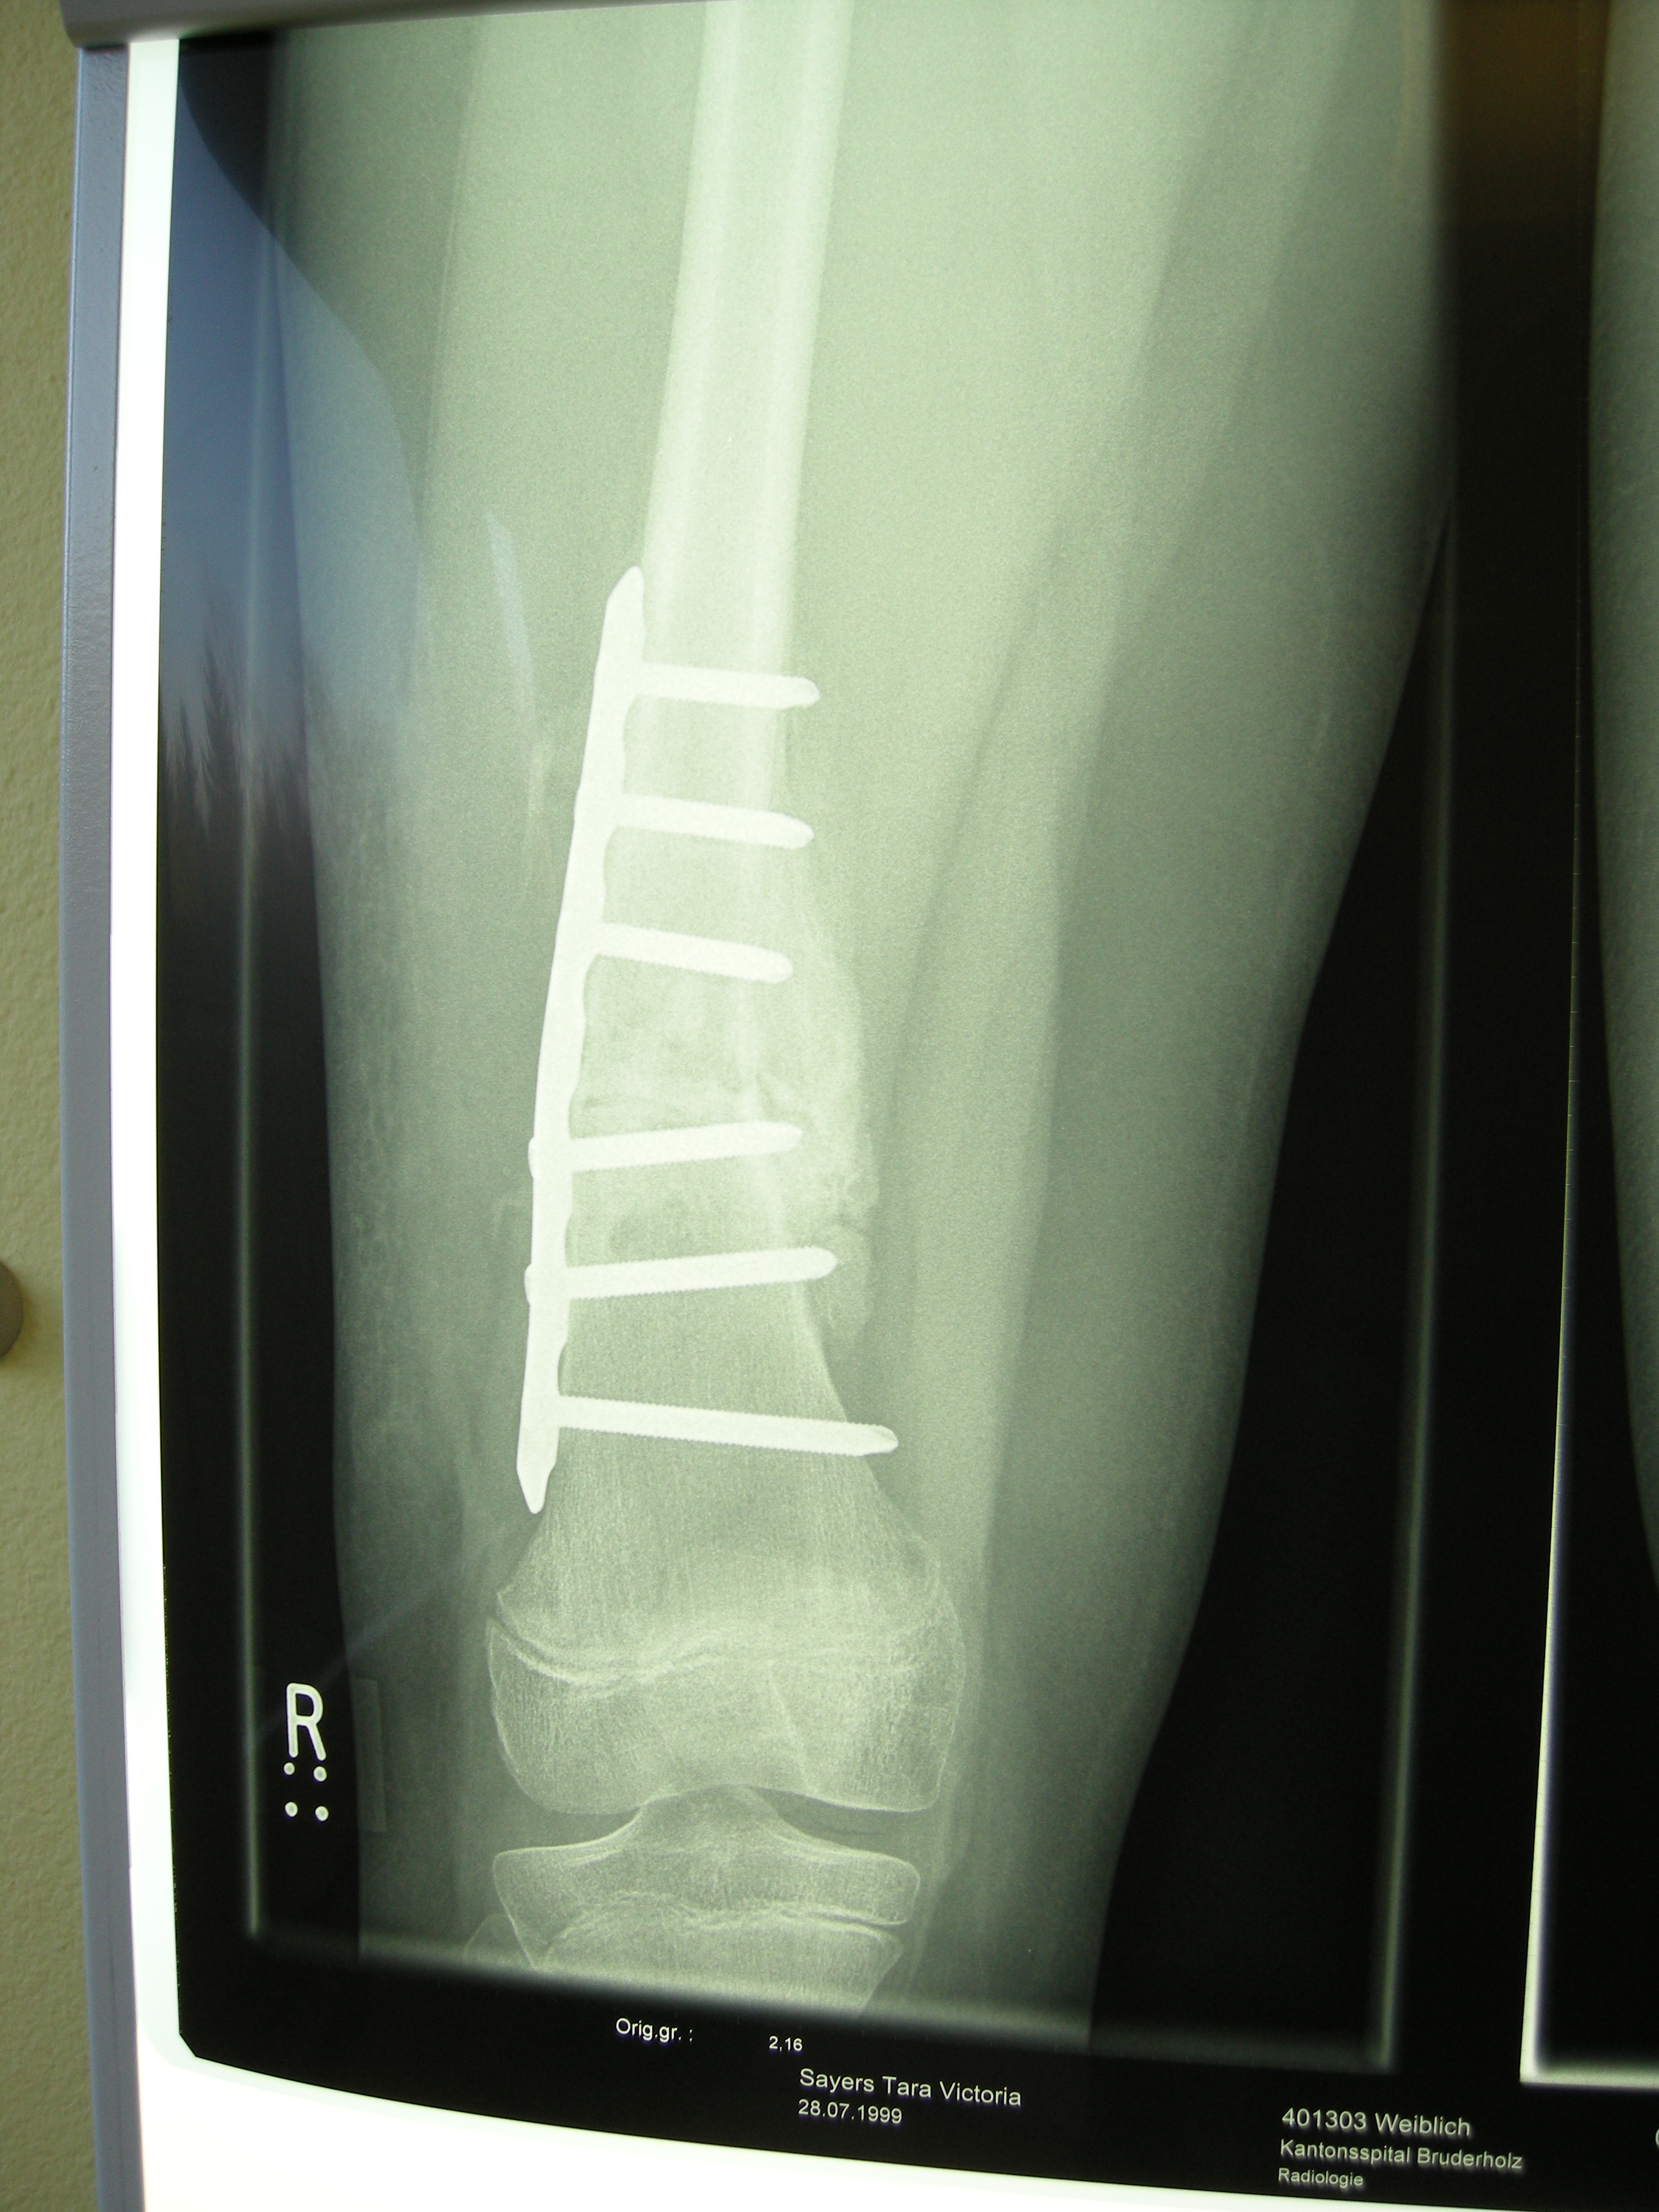

XRays

2009